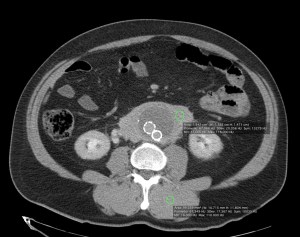

Paciente de 75 años de edad que acude a urgencias por cuadro de abdomen agudo. AP: Operado de hernia inguinal hace 48 horas. Alteración de las constantes vitales, se sospecha perforación por lo cual se demanda TAC de abdomen.

Veamos los hallazgos en una TAC con y sin contraste:

Decimos masa en este caso, aunque se podría pensar que es un sangrado de aneurisma. ¿Por qué no es esta última opción? Observar en primer lugar las paredes de la aorta delimitada por calcio, es decir, sus paredes están calcificadas. Para que pudiésemos hablar de aneurisma, nuestra masa debería tener el calcio en su perifería, Signo del calcio tangencial, y esto no ocurre. La aorta está calcificada y no está sangrando, lo cual se ve reforzado por el hecho de que la masa rodea de una manera uniforme y armoniosa la aorta; un sangrado no sería tan regular, no rodearía de una manera tan perfecta la arteria y además habría predominio de sangrado hacia algún lado de nuestra aorta. Solución: Estamos ante un linfoma.